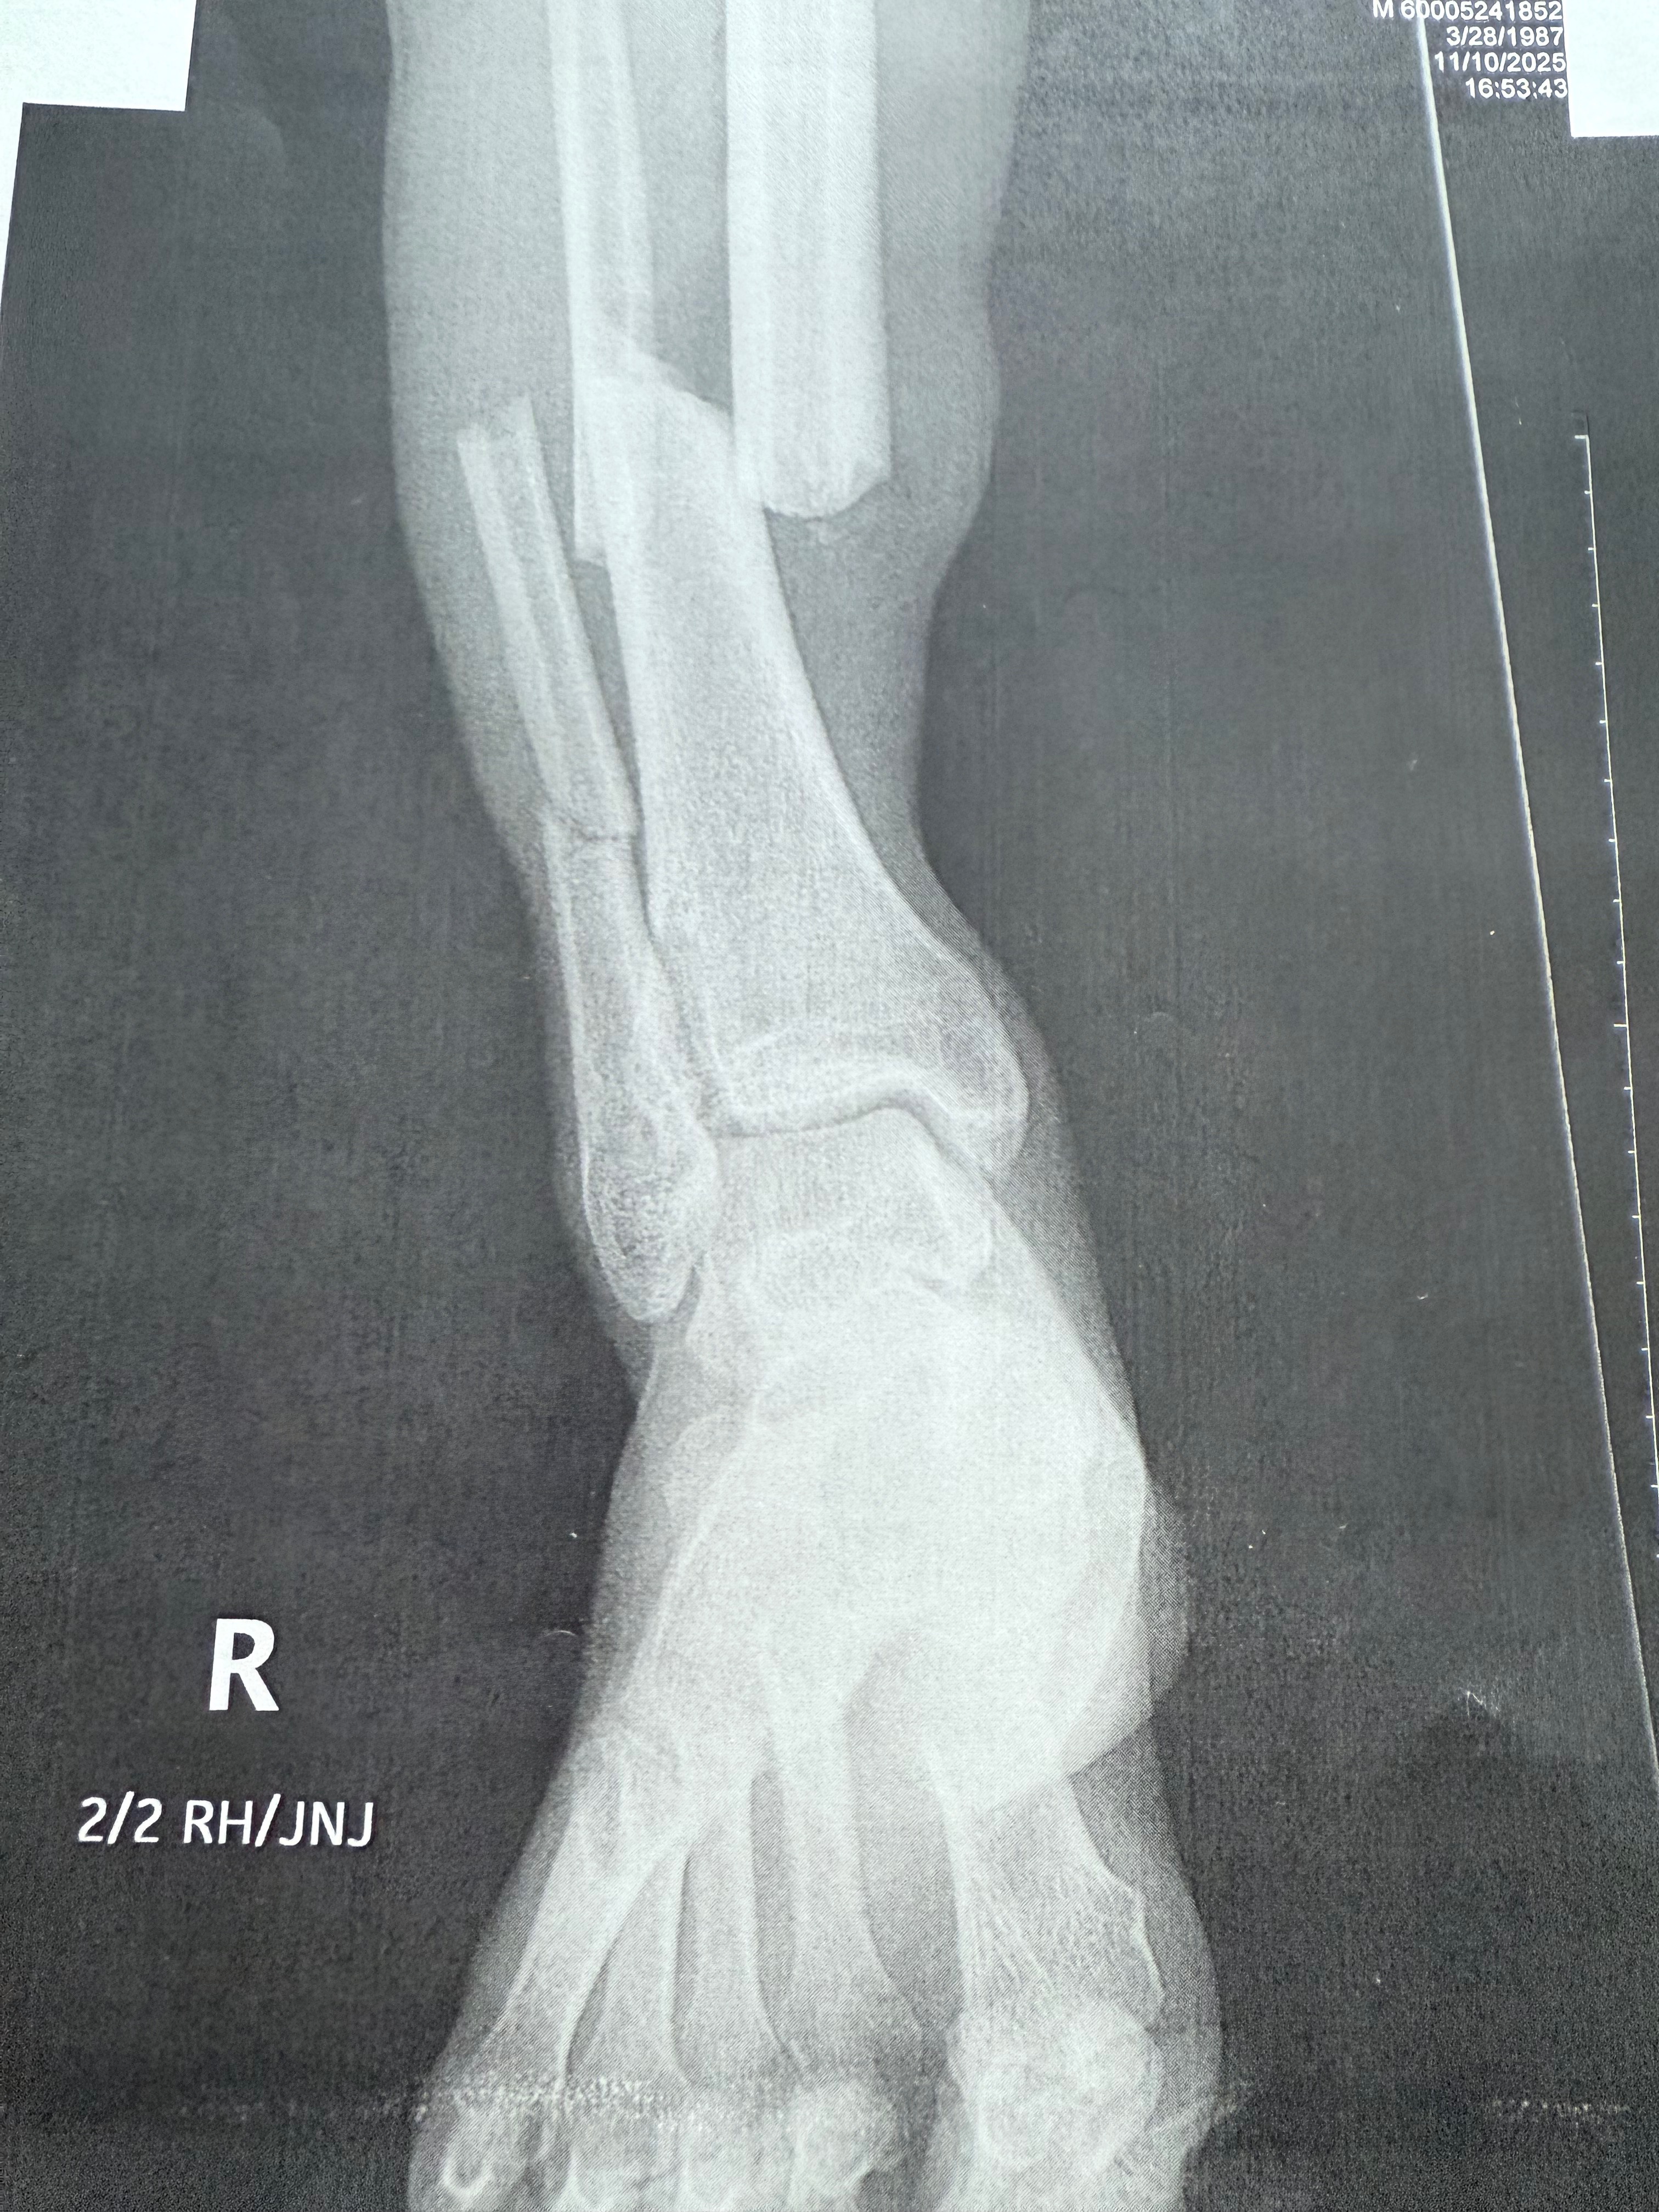

This GoFundMe is set up for Raymond. On 11/10/2025 at about 4:30 pm Ray was riding his bike home & an uninsured driver hit Ray with his car. The man stayed & cooperated with police but told them he has no insurance to pay for any of this. Ray had to have surgery to repair his leg. He broke his tibia and fibula in 3 different spots.